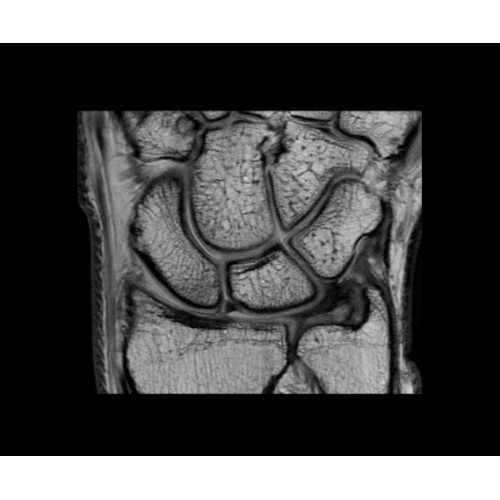

SIGNA PET/MR 3.0T — это гибридная система, в которой совмещаются две принципиально разные технологии — магнитно-резонансную томографию (МРТ) и позитронно-эмиссионную томографию (ПЭТ). Система отличающийся высокой чувствительностью и эффективностью и предназначена для диагностики в области онкологии, неврологии, кардио-васкулярных исследований, исследований воспалительных процессов.

Компания GE Healthcare представляет революционную, полностью интегрированную систему SIGNA PET/MR1, в которой сочетаются времяпролетная технология (TOF) и возможности напряженности магнитного поля 3.0 Тл. Мы поможем вам поднять исследования на более высокий уровень. SIGNA PET/MR позволяет достичь впечатляющей точности и скорости исследований, а благодаря новейшей технологии реконструкции Q.Clear2 качество изображений улучшается в два раза. Кроме того, в систему включен полный набор клинических приложений и гибких катушек для проведения любых видов исследования, открывая для вас возможности визуализации, о которых вы даже не догадывались.

В систему SIGNA PET/MR встроены запатентованные детекторы кремниевого фотоумножителя (SiPM) и сверхчувствительные кристаллические сцинтилляторы на основе лютеция толщиной 25 мм. Благодаря этому обеспечивается исключительная чувствительность и возможность использования времяпролетной диагностики (TOF).

Кроме того, в результате использования технологии TOF и инновационной технологии реконструкции Q.Clear вы сможете добиться прекрасного соотношения сигнал/шум. А благодаря технологии нулевого времени эхо (ZTE) визуализировать костную структуру без ионизирующего излучения. Все эти разработки для улучшения качества сканирования и точности анализа помогут вам использовать весь потенциал ПЭТ/МРТ.